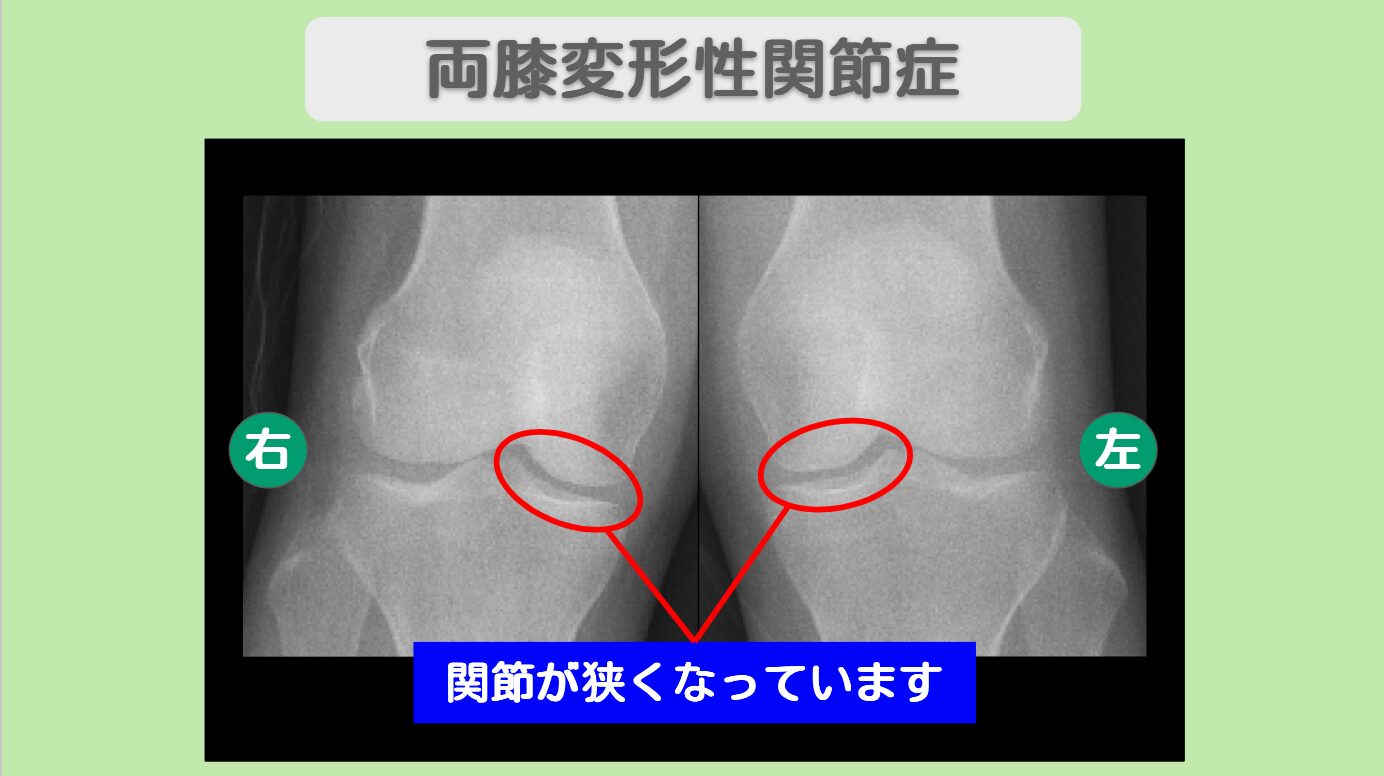

両膝の痛みが完全消失! 両変形性膝関節症 50代女性

数年前から両膝の痛みに悩まされ、立ち仕事が辛くなっていた50代の患者様。幹細胞治療によって、両膝の痛みが完全に消失しました。右膝は10段階中4だった痛みが0に、左膝も6だった痛みが0になり、「走った後も全く痛みを感じなくなりました」とのお声をいただきました。

レントゲン所見

<治療内容>両膝に5000万個細胞を計2回投与+PRP

両膝に5000万個ずつ、幹細胞を計2回投与いたしました。